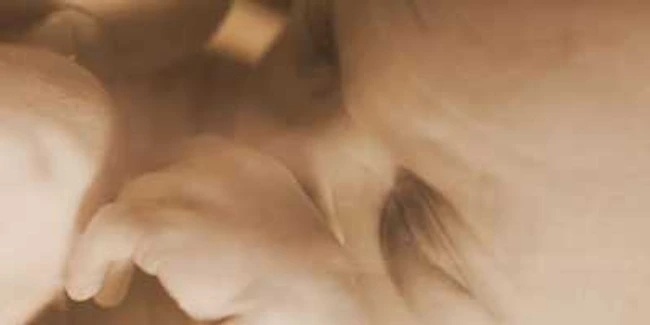

Ecografia efectuată în al doilea trimestru al sarcinii ne arată întregul bebeluş

Aceasta ecografie ne arata intregul bebelus,fiind vizualizate si apreciate bratele , manutele,picioarele;sunt masurate o multime de diametre la nivelul cutiei craniene,al abdomenului.Foarte importanta este examinarea inimii(este unul din momentele cheie in excluderea malformatiilor cardiace).